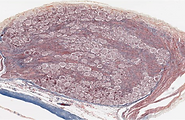

Ganglio cerebroespinal

Ganglio Cerebroespinal- Tricromico Masson- 20X

Ganglio Cerebroespinal- 40X